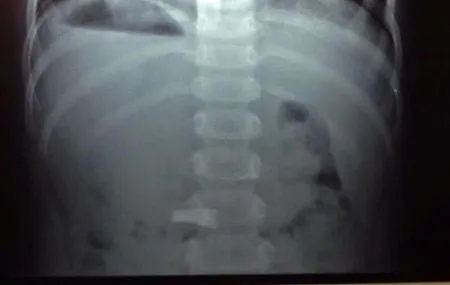

Sau đó cháu Mai Quyên được chuyển đến Khoa ngoại tổng hợp, Bệnh viện nhi Hải Phòng để cấp cứu. Kết quả chụp X.Quang cho thấy chiếc cặp đã nằm ngang yên vị trong dạ dày của bé. Các bác sĩ tại đây đã ưu tiên việc theo dõi để mong muốn chiếc cặp sẽ theo ra bằng đường hậu môn khi bé đi vệ sinh. Sau gần 2 ngày theo dõi, chiếc cặp vẫn không có biểu hiện tự ra như mong muốn, kế hoạch mổ lấy dị vậy cho bé đã được tính tới.

Kết quả chụp  X.Quang cho thấy chiếc cặp yên vị quay ngang trong dạ dày bé